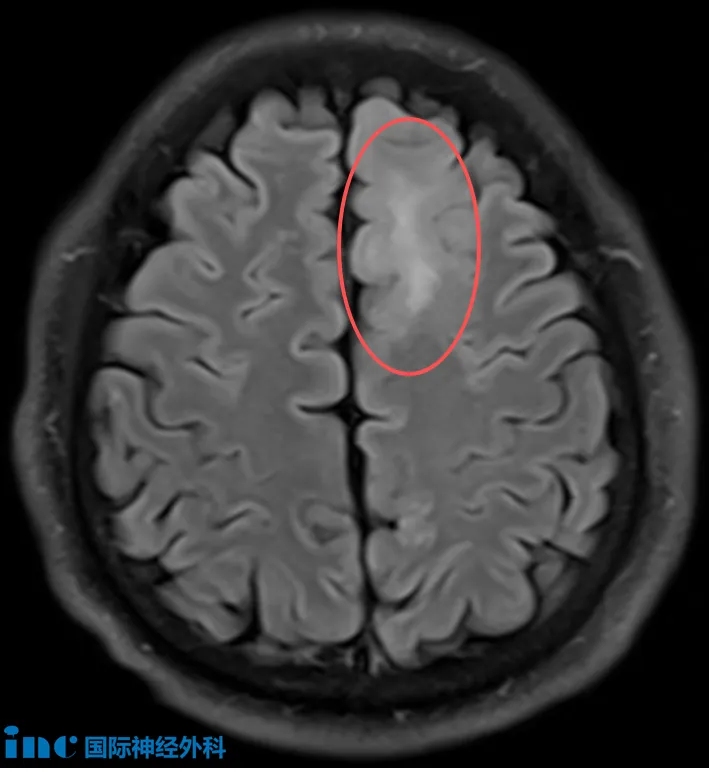

48岁的孙先生在本地医院头颅MRI体检中发现左侧额叶异常信号。为明确诊断,他接受PET-MRI检查,提示左额叶近中线异常信号,考虑低级别胶质瘤可能性大(不排除脱髓鞘病变)。随后头颅MRI确认左额叶皮层及皮层下存在边界不清的异常信号,范围约41×28mm,增强扫描未见明显强化。令家属担忧的是,孙先生近期已出现记忆力下降迹象。面对这一超过4厘米、性质未明的颅内病灶,究竟是什么病变?是否需要手术?

“归根结底,影像学检查无法提供百分之百的确定性。手术是获得明确诊断的唯一途径。即使影像提示肿瘤,我们仍不了解其分子特征,而这十分重要。我将尽可能多切除病灶,同时竭力避免神经功能损伤。”——INC巴教授